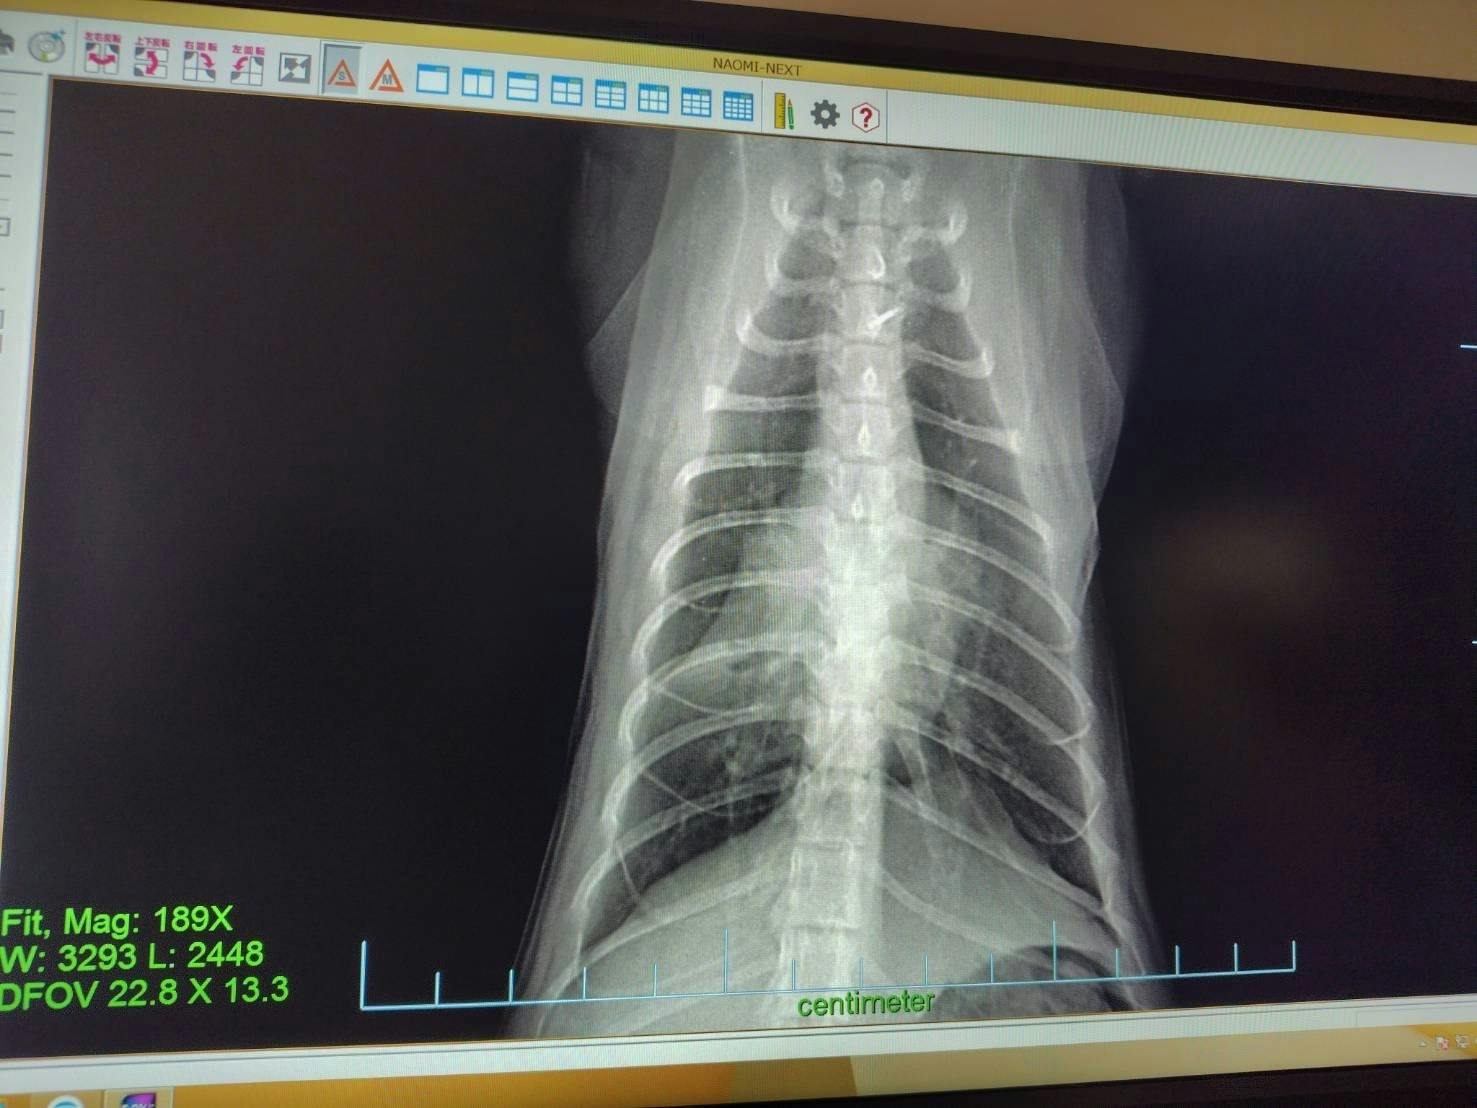

しっぽく肺炎と気管支炎発症!

2025/12/11 16:29うちに来た時から変な咳をするので病院に連れて行ったところ、以前に風邪を拗らせて肺炎と気管支炎を併発しているとのことです。前にも同じことがありました。美観nekoのタプタプちゃんです。ブリーダーかペットショップで風邪をきちんと治してもらってなくて肺が心臓に癒着してました。風邪をひかないように気を付けておけば喘息も治るのですが、癒着はしたままになります。しっぽくも来た時からメヤニも多いし気にはなってました。これから定期的な治療に入ります。抗生物質と喘息の治療です。ご支援のほどよろしくお願いします。 もっと見る